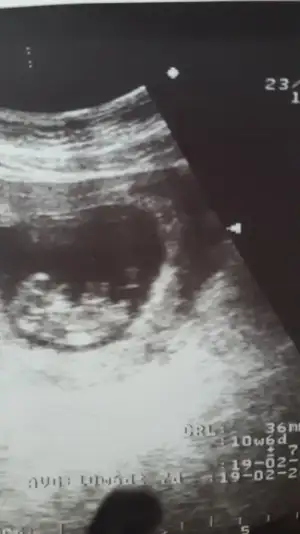

• 5B8C175B-215C-49C6-BC33-2647A93A0F77.webp

5B8C175B-215C-49C6-BC33-2647A93A0F77.webp

9,1 KB · Görüntüleme: 73